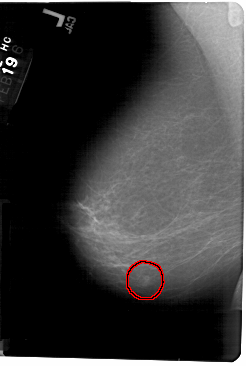

A_1346_1.LEFT_MLO

LEFT_MLO LINES 5476 PIXELS_PER_LINE 3676 BITS_PER_PIXEL 12 RESOLUTION 43.5 OVERLAY

FILE: A_1346_1.LEFT_MLO.OVERLAY

TOTAL_ABNORMALITIES 1

ABNORMALITY 1

LESION_TYPE MASS SHAPE OVAL MARGINS ILL_DEFINED

ASSESSMENT 4

SUBTLETY 4

PATHOLOGY BENIGN

TOTAL_OUTLINES 1

BOUNDARY